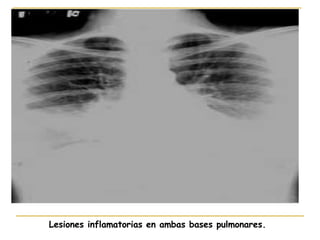

Lesiones inflamatorias en ambas bases pulmonares.

Lesiones inflamatorias enambas bases pulmonares.